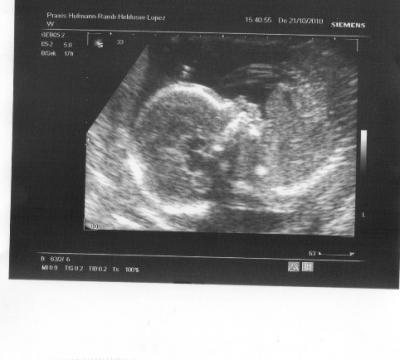

Also dem Bauchzwerg gehts prächtig! Hatte grad Schluckauf, als US gemacht wurde - total süß! Und wir haben ganz eindeuting ein Outing - wir bekommen einen Jungen!!! Lustigerweise haben auch alle außer mir selbst auf einen Jungen getippt! Danach waren wir direkt bei H&M und haben Jungsklamotten geshoppt! Ein richtig süßes Profilbild hab ich auch noch bekommen! Ach ja, den großen US will er erst in 2 Wochen machen, dann darf ich also wieder hin! :-))

Bild zu Zurück von der VU mit einem Outing!!! :-)) - Forum für März - Mamis